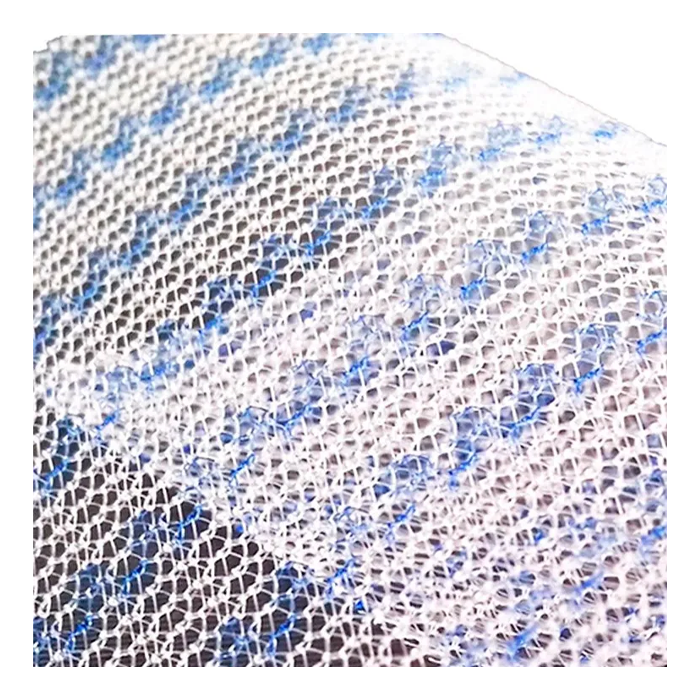

Эндопротез-сетка ЭСФИЛ лёгкий от компании «Линтекс» — это современное и надежное решение для пластики грыж и восстановления мягких тканей в абдоминальной хирургии. Изделие изготовлено из высококачественного монофиламентного полипропилена, что обеспечивает оптимальное сочетание прочности, биологической инертности и удобства для хирурга.

Сетка обладает пониженной плотностью и весом, что минимизирует количество инородного материала в организме пациента, способствуя более комфортному послеоперационному периоду и снижая риск таких осложнений, как хронический болевой синдром и ощущение инородного тела.

- Лёгкость и эластичность: Пониженная поверхностная плотность материала делает сетку более мягкой и податливой. Это упрощает её моделирование и фиксацию в операционной ране, обеспечивая точное анатомическое соответствие.

- Оптимальная интеграция в ткани: Макропористая структура (размер пор более 1 мм) позволяет свободно прорастать соединительной ткани и сосудам через ячейки сетки. Это способствует формированию прочного рубца и снижает риск инкапсуляции, инфекции и серомы.

| Материал | Монофиламентный полипропилен |

| Структура | Макропористая, нерассасывающаяся |

| Цвет | Белый, синий (может варьироваться в зависимости от партии) |